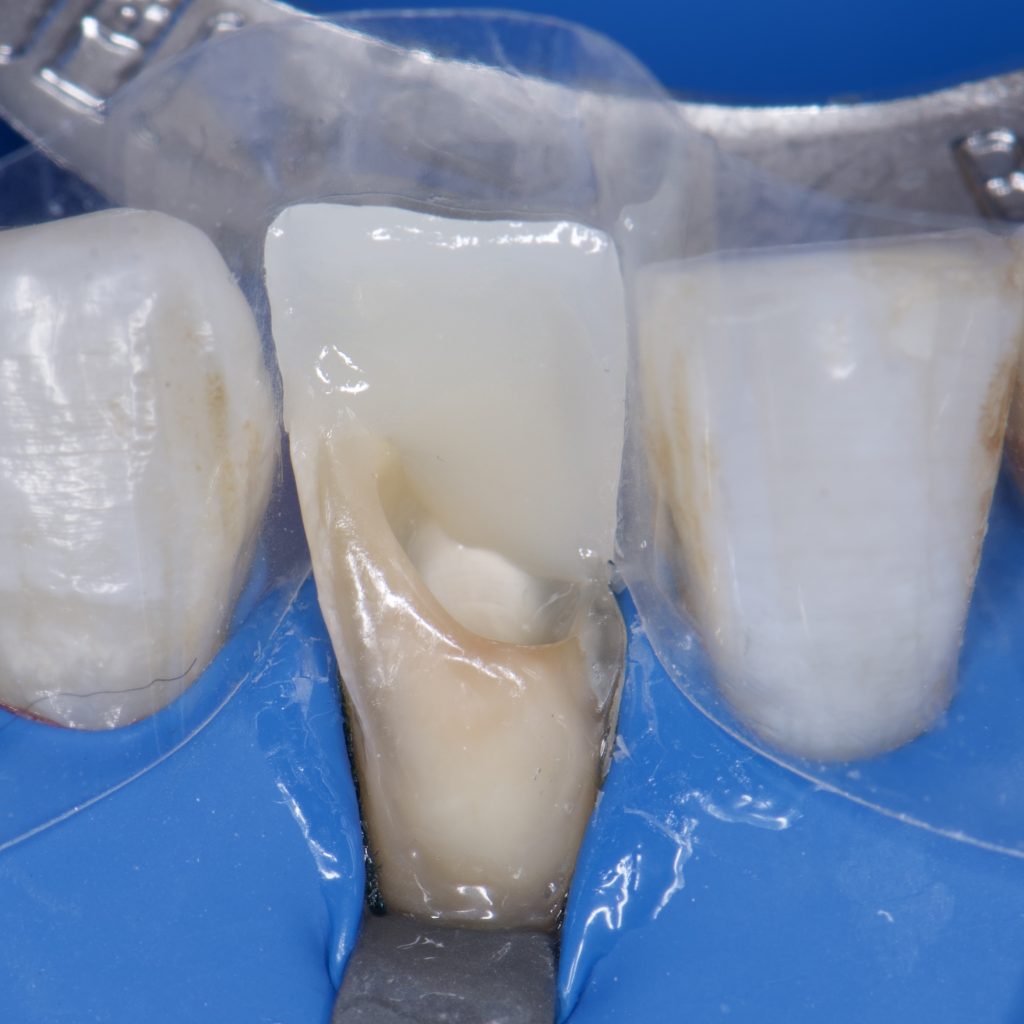

– SE clearfil bond

– Ribbond

– Direct composite restoration, layering technique